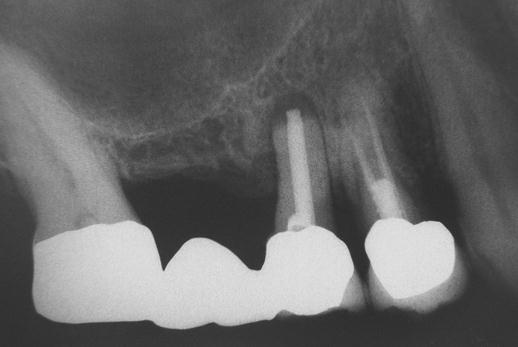

- Uzavřený, interní, vnitřní, crestální sinus lift

- Otevřený, externí, vnější, laterální sinus lift

Souprava pro laterální přístup k sinus liftu, speciálně navržena pro bezpečný a méně invazivní laterální přístup k nadzdvihnutí membrány sinu. LAS Kit nabízí v závislosti na anatomii dutiny ústní a plánech operace různé využití.

CAS Kit

Souprava pro krestální přístup k operaci sinus liftu tím, že se vytvoří v kosti kónický odštěpek, kterým lze membránu bezpečně nadzvednout.